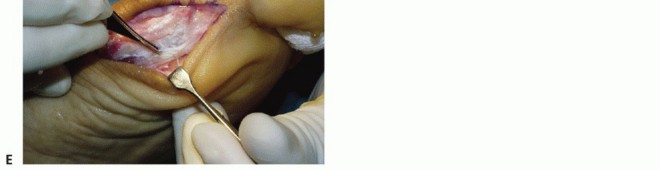

crosses plantarly along the flexor crease at the base of the phalanx (TECH FIG 1A). Take extreme care to identify and protect the plantar-medial digital nerve (TECH FIG 1B).

Make a longitudinal incision at the level of the abductor hallucis tendon (TECH FIG 1C). This allows both intra- and extraarticular examination of the plantar complex.

Fully define the extent of the injury (TECH FIG 1D).

Thoroughly examine the FHL tendon for longitudinal tears (TECH FIG 1E). In our experience, longitudinal tears of the FHL tendon are most commonly associated with a late presentation of turf toe injury in which the FHL is subjected to frequent greater than physiologic stretching as a result of the lack of plantar restraint of the MP joint.

TECH FIG 1 • A. Planned hallux incision. This hockey stick or J incision allows full exposure of the medial and plantar aspect of the MP joint. The tibial sesamoid is outlined. B. Intraoperative photograph showing identification and mobilization of the plantar-medial digital nerve. C. Longitudinal incision at the abductor hallucis and capsule allows visualization of the joint. D. After exposure, the extent of the injury must be defined. This involves identifying each element of the plantar complex to determine its integrity. E. The FHL tendon is inspected for longitudinal tears and repaired primarily if necessary. -